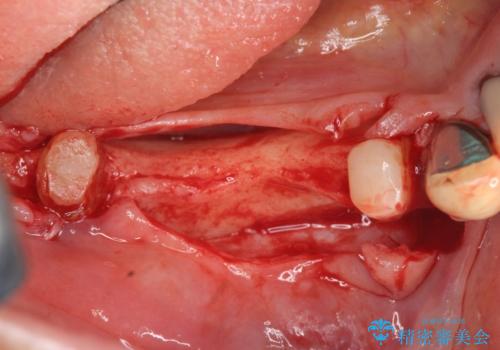

また骨の問題だけでなく、完成後に歯ブラシがしやすいよう歯ぐきの移植も行いよりインプラント周囲の環境が安定するよう環境を整える治療計画を立てます。

また、機能したインプラントを長持ちさせるために清掃性を高めるために硬い歯ぐきを移植することは非常に有効です。